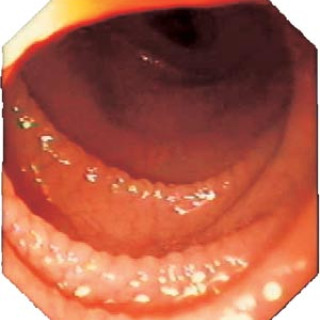

Cøliaki er en av de vanligste kroniske sykdommene i den vestlige verden. Sykdommen har en prevalens på 1 : 200 eller hyppigere, og enhver lege vil bli stilt overfor pasientenes varierte kliniske bilde og den spesielle behandlingen (1, 2). Som ved matallergi eller matintoleranse, blir pasienter med cøliaki symptomfrie ved å unngå den skadelige komponenten. Vellykket behandling med glutenfri kost forutsetter at cøliakidiagnosen er riktig, at pasienten har fått tilstrekkelig kostveiledning og at pasienten er motivert for kostendring. Det er legens ansvar å sørge for at pasienter med cøliaki eller...